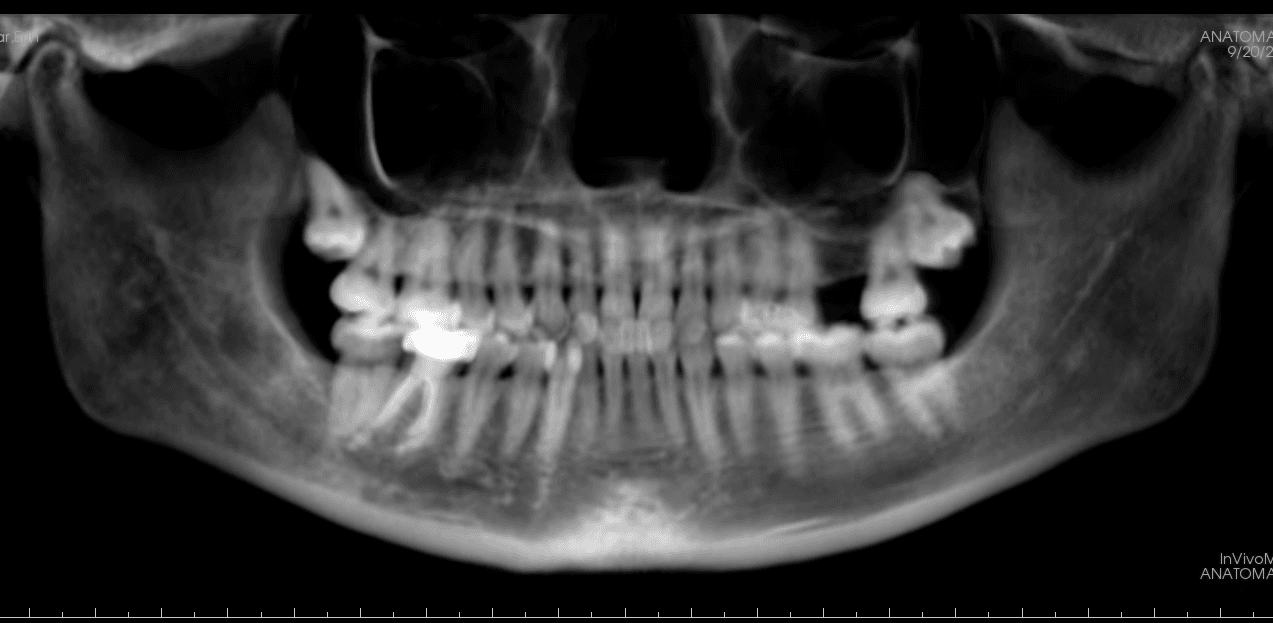

Diagnosis: Lower anterior crowding, LL3 crossbite, deep bite, missing UL6.

X-RAYS